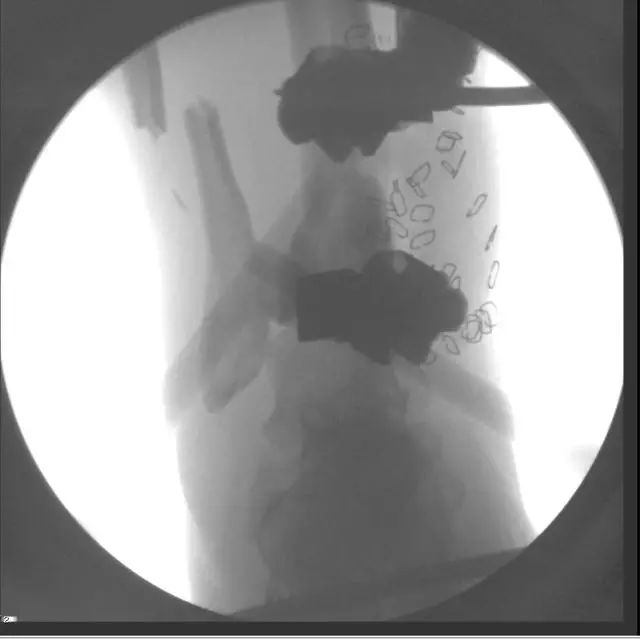

X 线片可见骨块寄养在自体下腹部皮下

创口清创、大量冲洗以后一期外固定支架固定,缺损区域抗生素骨水泥填充

二期回植,更换为钢板内固定

回植后 8 个月,骨折无感染迹象

另一例 48 岁男性,大块的胫骨骨折块,12 周以后从腹部皮下取出骨折块,图 B,去除再血管化的软组织